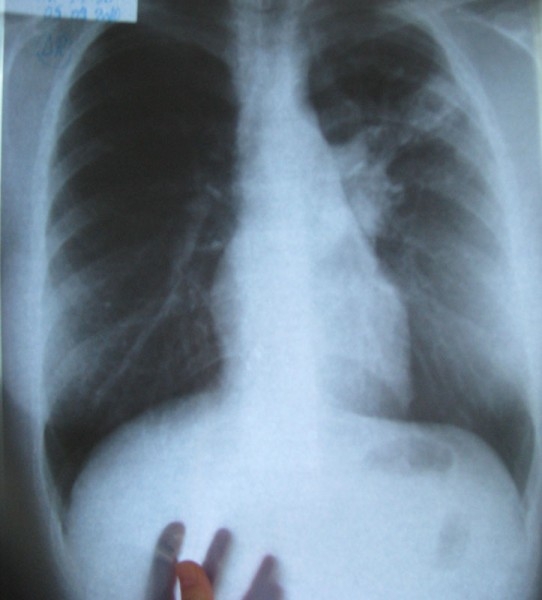

Tuberculoza afectează de la un an la altul din ce în ce mai mulţi brăileni. Numărul bolnavilor a crescut în anul 2015, comparativ cu 2014, potrivit unor cifre furnizate de Spitalul de Pneumoftiziologie. Pentru a împiedica răspândirea acestei boli, dar şi pentru a identifica posibilele focare din judeţ, conducerea unităţii spitaliceşti ia în calcul pentru 2016 să meargă din localitate în localitate şi, cu sprijinul autorităţilor locale, să identifice persoanele afectate de TBC.

Suspecţii de tuberculoză vor fi transportaţi fie la Dispensarul TBC Făurei, fie la Dispensarul TBC Brăila, unde vor fi supuşi unui examen medical de specialitate şi unui examen radiologic pulmonar. În funcţie de rezultate, cei depistaţi cu modificări radiologice susceptibile de TBC vor efectua gratuit şi alte investigaţii medicale. Brăilenii în cazul cărora se va confirma prezenţa bolii vor fi spitalizaţi, trataţi şi monitorizaţi gratuit.